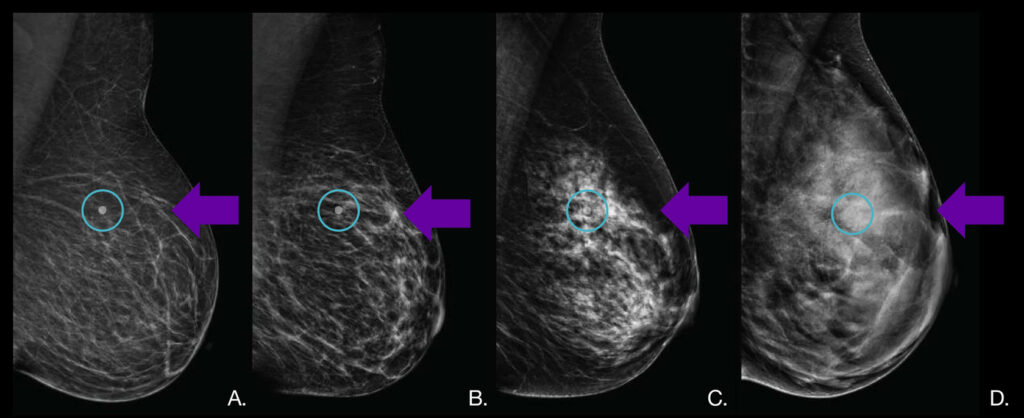

Mammograms are an important tool for early breast cancer detection, but they don’t always show everything—especially in women with dense breast tissue.

On a mammogram, dense tissue appears white, just like cancer, which can make small abnormalities harder to detect.

ABUS is a supplemental screening tool that uses sound waves to create 3D images of the breast. These detailed images help specialists see through dense tissue more clearly and support earlier, more accurate detection.